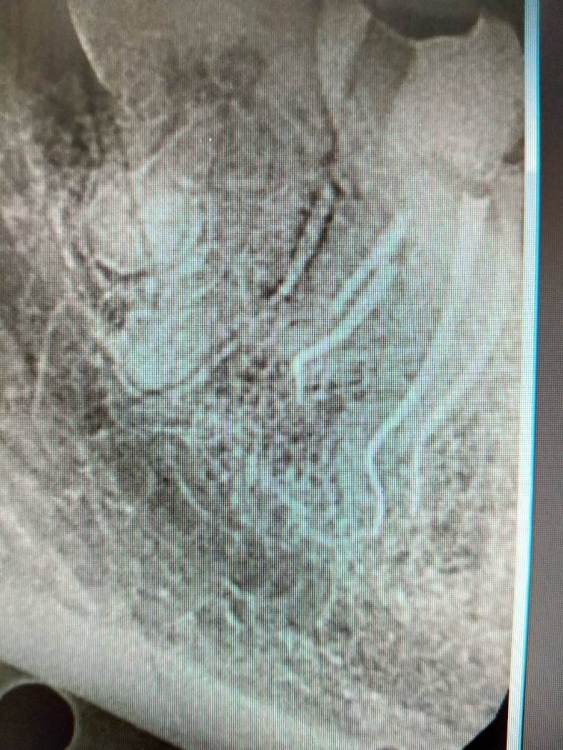

4.7 пульпит.2 визита SX -> S1 короткий -> scout -> Coco+2 плюс патфаилы 1-2 номер, иногда даже в ручном режиме до "0" по аплоку, финиш на 25.02 профайл руками.Гибридная паковка с  эйчем.

1.3.jpg